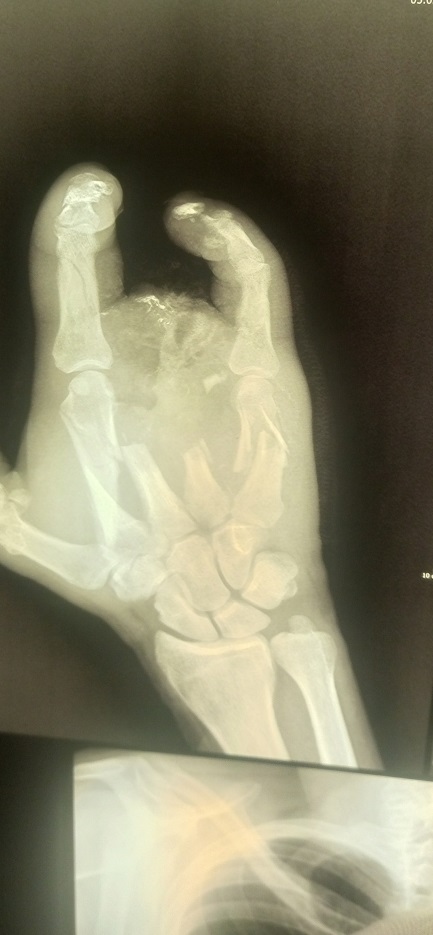

Рука Алексея после ранения на войне